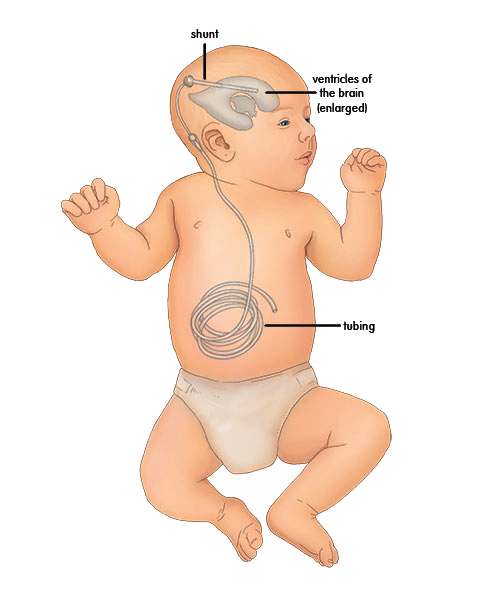

Вентрикуло-перитонеальный шунт: Показания и применение

Раздел: Фотоальбом решений